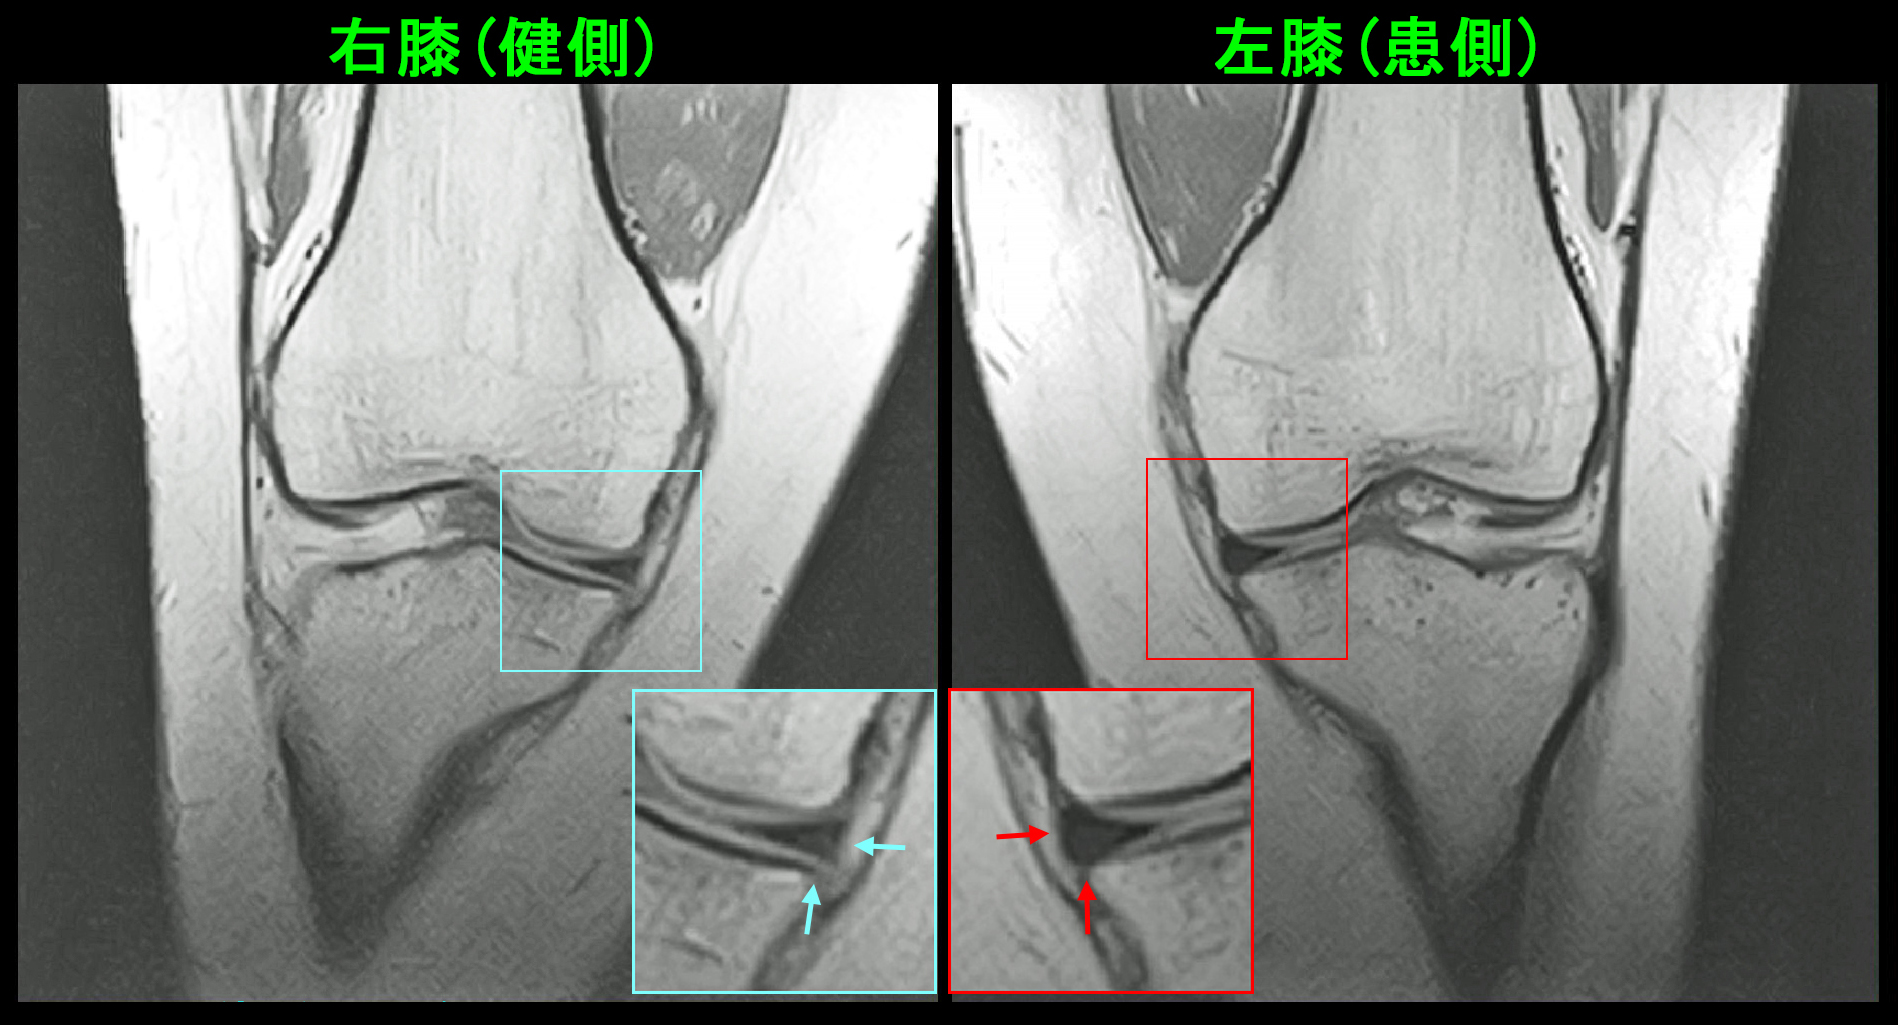

次の症例が服薬のみで半月板亜脱臼の痛みが治癒した患者さんです。17才のサッカー部の男子生徒です。令和7年12月27日から静岡遠征があり、初日の試合で全力疾走していて後方からスライディングされて前方に転倒し、右膝を捻挫し、以後は見学していたとのことでした。1月6日に当院を受診されました。1月10日のMRI検査(PDの冠状断)で右半月板の軽微な亜脱臼が確認されます。

17才男 MR1.jpgPD矢状断では内側半月板の関節包の接合部に軽度の損傷所見(左に比して接合部が白くなっています)が確認され、接合部損傷に伴う半月板亜脱臼と診断されました。

17才男 MR2.jpg

自転車で転倒の女子高生の経験と94才の女性の腰痛の経験から、しっかりとプレドニゾロンを処方する方針としました。鎮痛剤のロキソニン2錠とプレドニゾロン5㎎2錠と増量して1週間、2週目はロキソニン2錠とプレドニゾロン2.5㎎2錠で1週間の処方を行いました。この患者さんは5週後に手指痛で受診されましたが、右膝痛は治癒しサッカーには問題はないと報告してくれました。半月板亜脱臼も服薬で治療できる可能性があると知れた症例となりました。